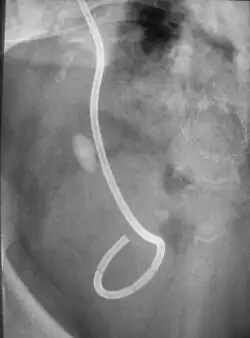

- Steinstraße – unerwünschter Nebeneffekt der extrakorporalen Stoßwellenlithotripsie, bei dem sich Teile des zertrümmerten Steins im Harnleiter sammeln.